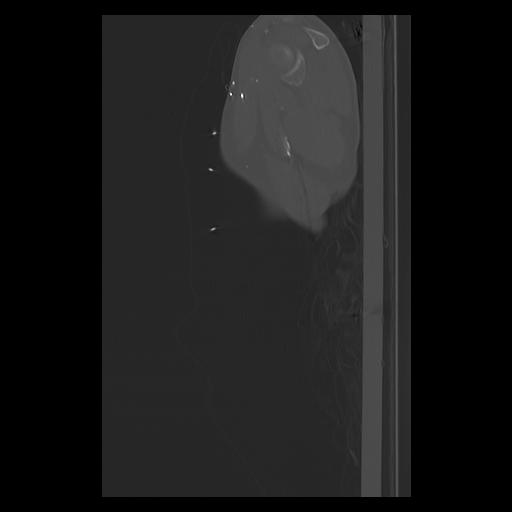

33 PULMON,CE,Sagittal,3.000,PULMON,Sagittal,